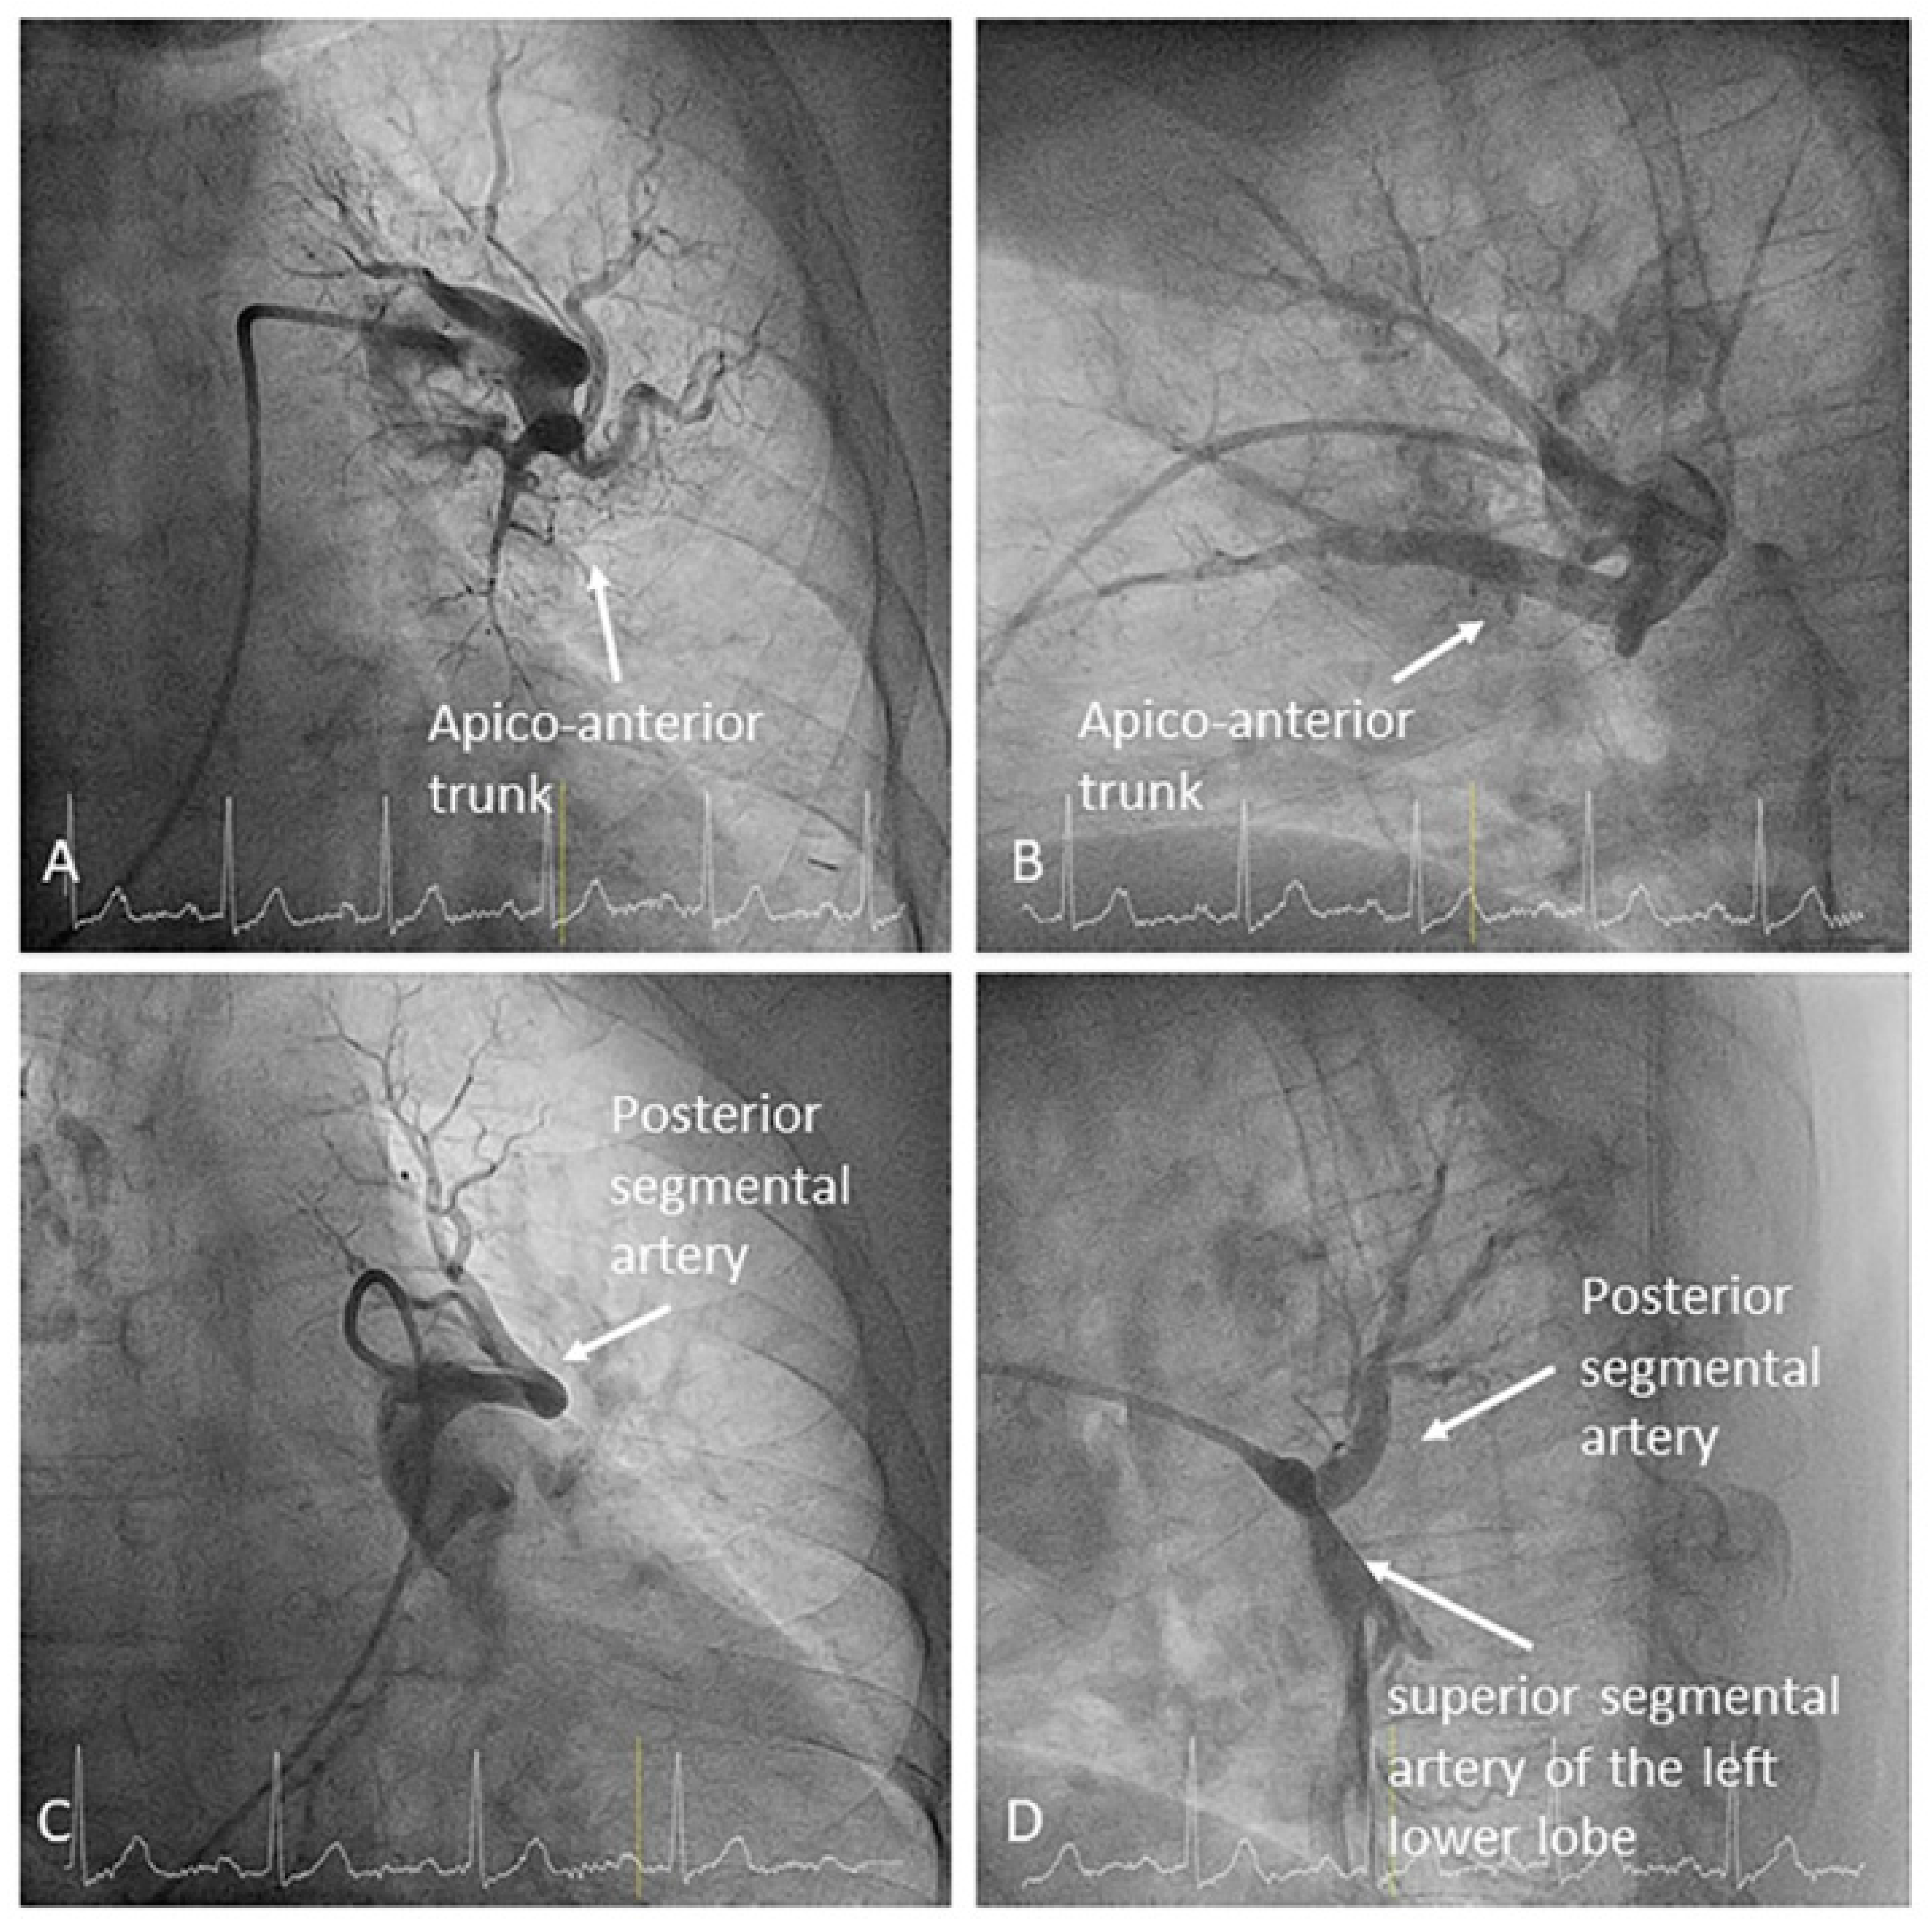

- Left upper lobe. The apico-posterior trunk (A1/2) is easily cannulated in the AP view. We should rotate the MP-A2 catheter counterclockwise in the proximal segment of the LPA to make the tip face upwards (Figure 23). The apical and posterior segmental arteries (A1 and A2) are well visualized by filming in the AP and lateral views. The anterior segmental artery (A3) is engaged more easily with the Judkins left catheter (JL) 3.5 or 4. Position the JL below the aortic arc in the AP view with the distal tip facing the left lateral chest wall. Rotate the catheter counterclockwise and withdraw it slightly. The distal tip of the catheter will climb 2–3 cm, engaging the anterior segmental branch (A3) (Figure 24). Film this branch in the cranial RAO and lateral views.